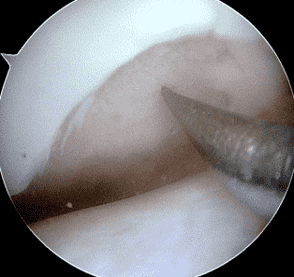

A 32-year-old man suffered a traumatic chondral injury to the medial femoral condyle that was treated with an osteochondral allograft 20 months previously. Representative images from a current knee MRI include (1A) coronal fat-suppressed fluid-sensitive and sagittal (1B) T1-weighted, (1C) proton density-weighted, and (1D) T2-weighted sequences. Are the post-operative MRI findings normal and expected, or abnormal and pathologic? Based on these images, would you characterize the procedure as a success or failure?

Figure 2: (2A) On the coronal image, the margins of the osteochondral graft are faintly visible (arrowheads). Both the graft and underlying bone show mild marrow edema, an expected finding. (2B) The T1-weighted image shows continuity of the marrow in the graft (asterisks) with the underlying bone, indicating osseous integration. A bioabsorbable pin (arrow) used for graft fixation is partly visible. (2C) The proton density-weighted image shows a low signal intensity seam (black arrow) between the native cartilage and transplant, as well as a defect in the subchondral bone plate of the graft (red arrow) where the pin was drilled, both normal findings. (2D) The T2-weighted image shows a smooth, congruent articular surface (arrows), restoring the normal anatomy, and a tiny subchondral cyst. No findings are present to suggest graft failure. The patient’s current symptoms were attributed to pathology elsewhere in the joint (not shown).